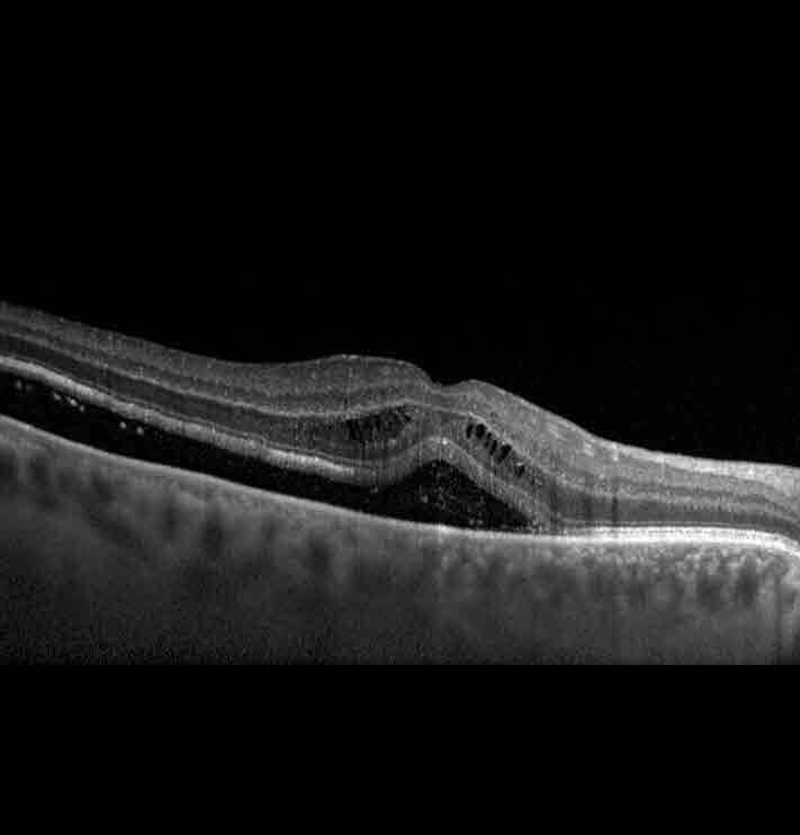

• التصوير المقطعي للاتساق البصري (OCT). يُعد هذا الاختبار أسلوبًا رائعًا لالتقاط صور دقيقة للشبكية بغرض تشخيص الأغشية فوق الشبكية، والثُّقوب البقعية، والتورّم البُقعي (الوذمة)، ومراقبة مدى الانحلال البقعي السلي المرتبط بتقدم السن، ومراقبة الاستجابات نحو العلاج.